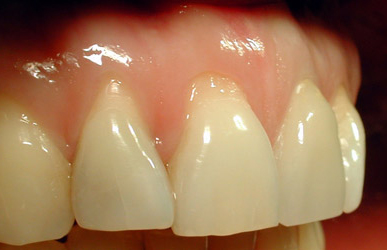

Cas 3 : 1 incisive centrale

Une copie de la dent symétrique permet une symétrie des deux incisives centrales